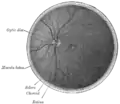

Interiorul jumătății posterioare a bulbului ochiului stâng. Venele au aspect mai închis decât arterele.